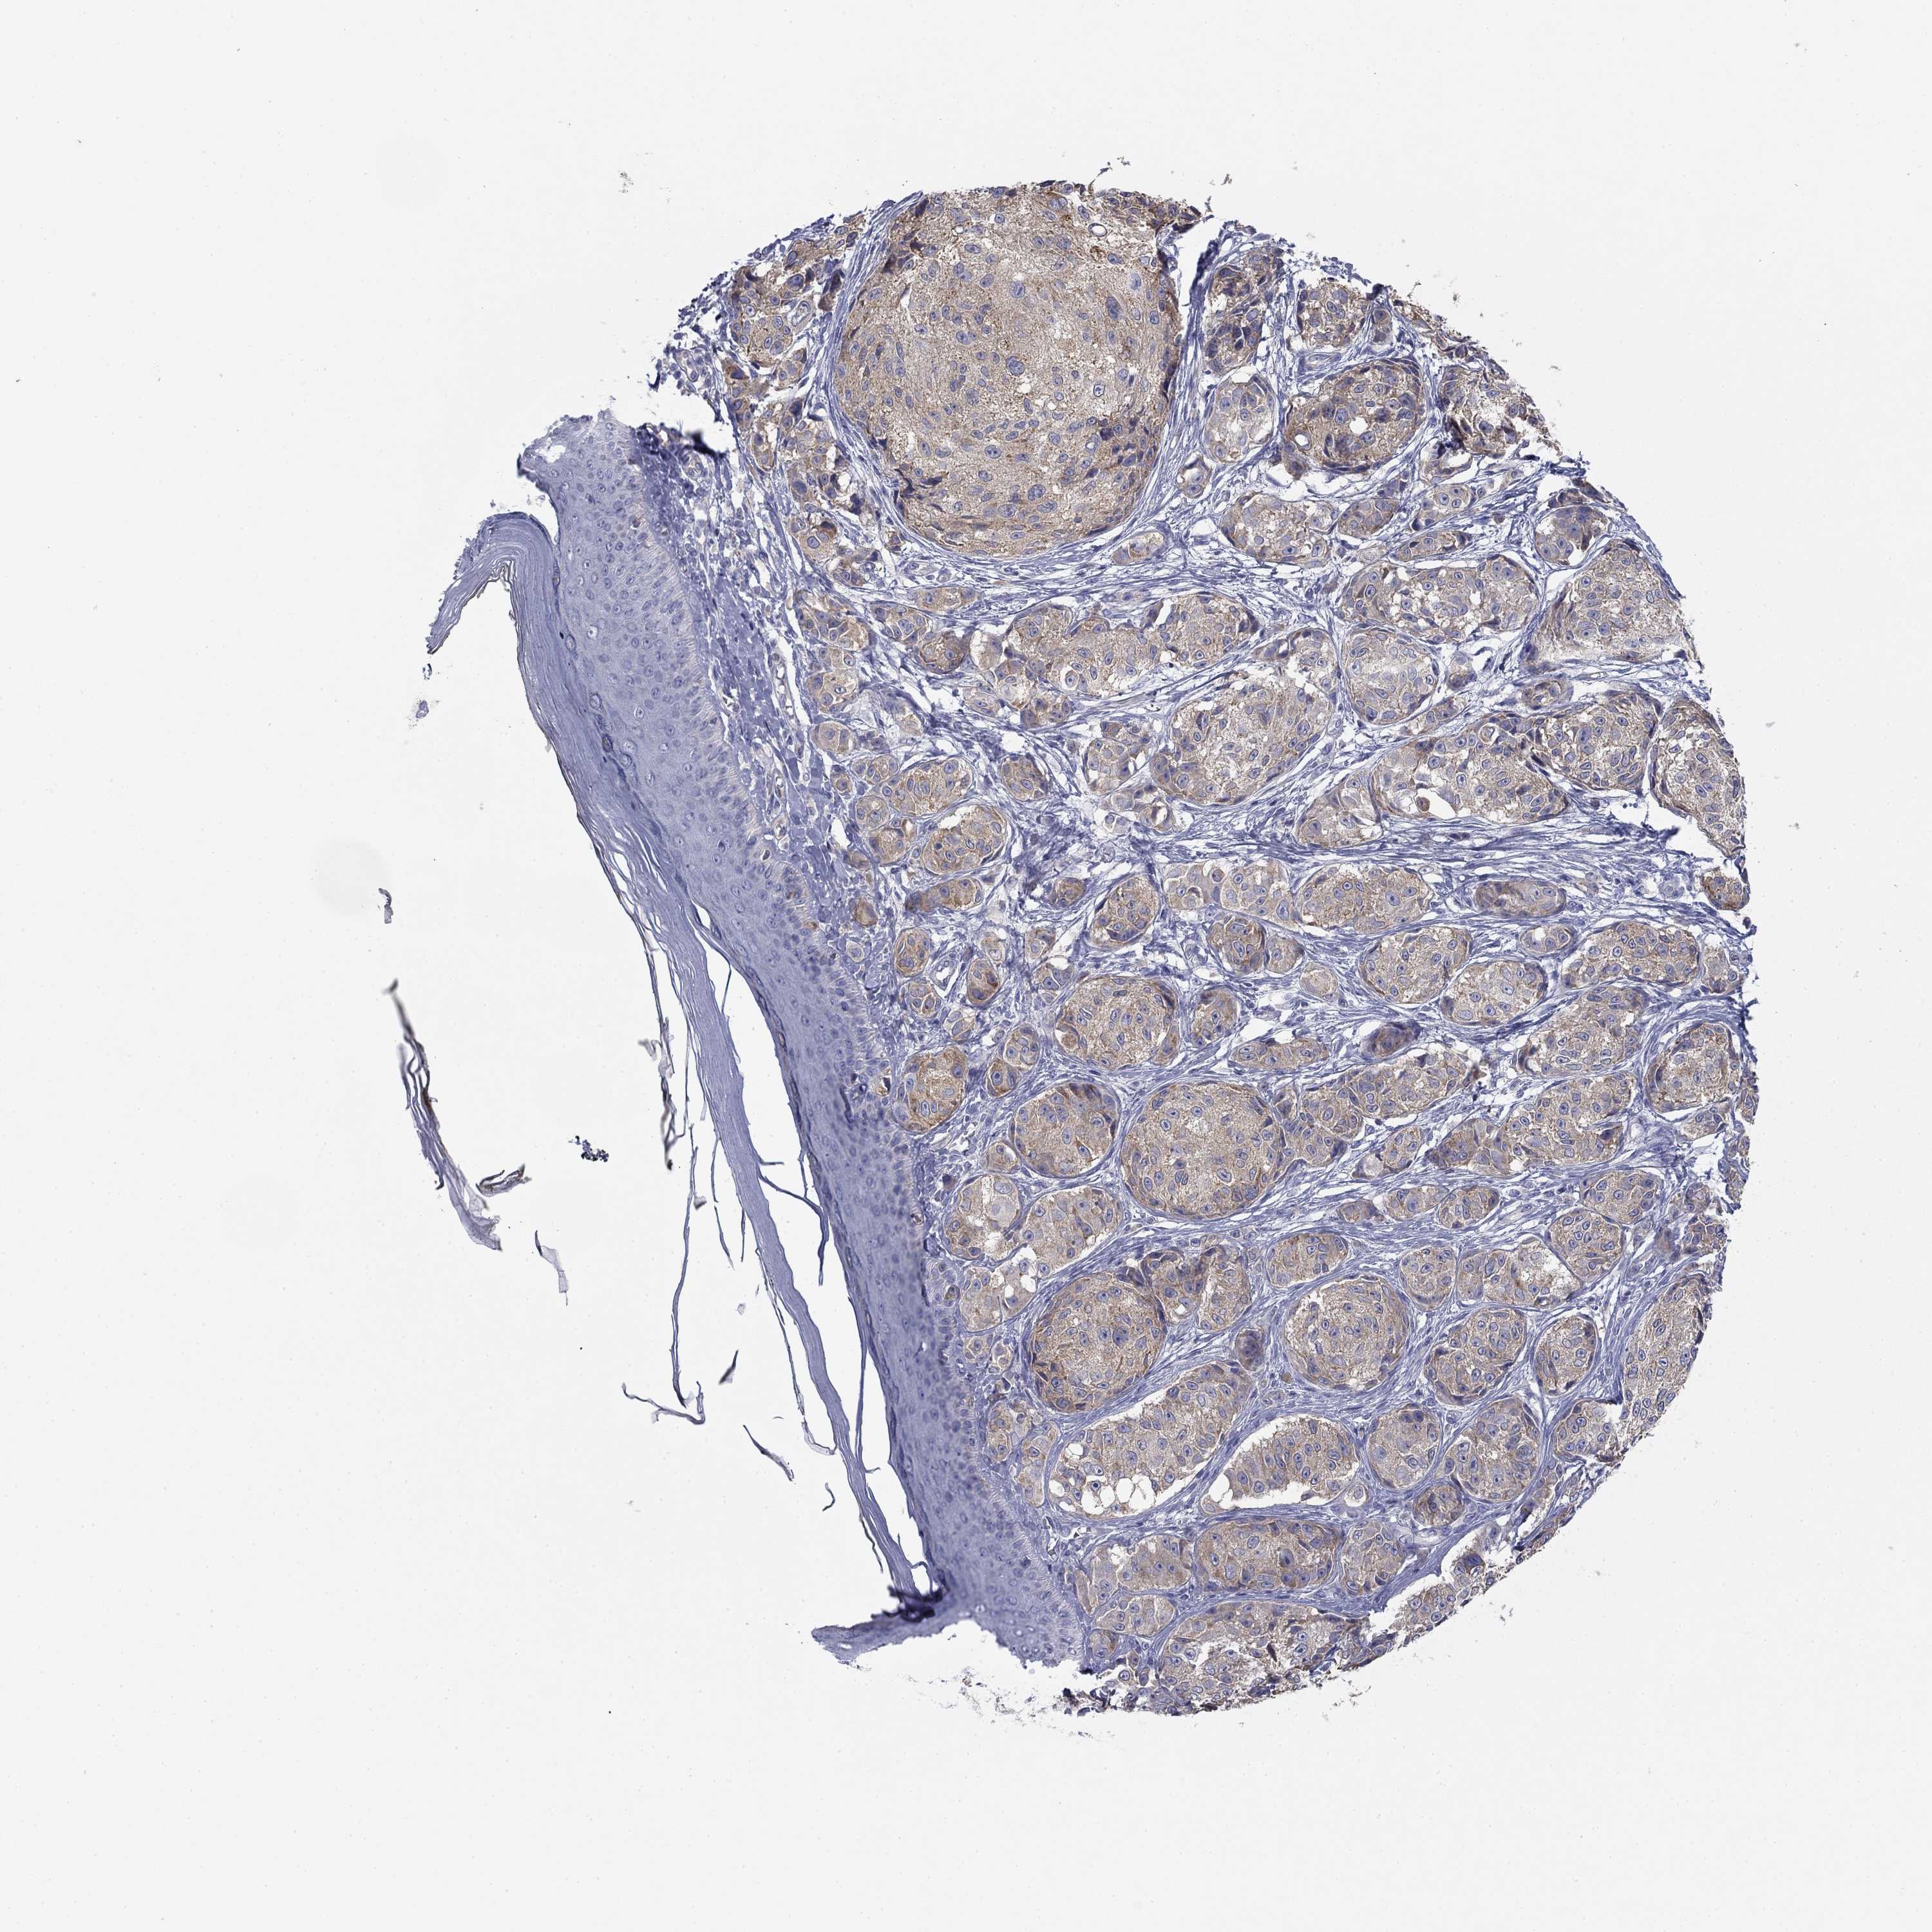

MELANOMA - Protein expressioni

A mouse-over function shows sample information and annotation data. Click on an image to view it in a full screen mode. Samples can be filtered based on level of antibody staining by selecting one or several of the following categories: high, medium, low and not detected. The assay and annotation is described here.

Note that samples used for immunohistochemistry by the Human Protein Atlas do not correspond to samples in the TCGA dataset.

Antibody stainingi

Antibody staining in the annotated cell types in the current human tissue is reported as not detected, low, medium, or high, based on conventional immunohistochemistry profiling in selected tissues. This score is based on the combination of the staining intensity and fraction of stained cells.

Each image is clickable and will lead to virtual microscopy that enables deeper exploration of all samples and also displays staining intensity scores, fraction scores and subcellular localization as well as patient and tissue information for each sample.

Antibody HPA003548

Antibody CAB017633

Staining

High

Medium

Low

Not detected

Intensity

Strong

Moderate

Weak

Negative

Quantity

>75%

75%-25%

<25%

None

Location

Nuclear

Cytoplasmic/membranous

Cytoplasmic/membranous,nuclear

Malignant melanoma, NOS

Malignant melanoma, Metastatic site